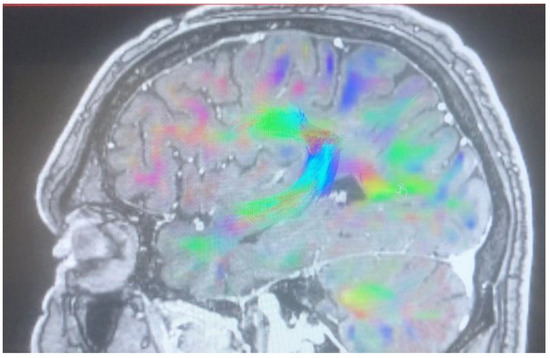

Changes in the anatomy of forceps minor before and after cingulotomy are presented in Figure 2 and Figure 3; moreover, arcuate fasciculus before and after cingulotomy is presented in Figure 4 and Figure 5.

Figure 3. Forceps minor after cingulotomy.

Brainsci 13 00044 g003